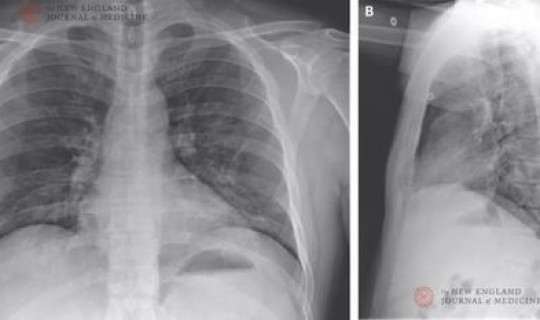

新型冠状病毒肺炎:简称“新冠肺炎” ,世界卫生组织命名为“2019冠状病毒病 ”,是指2019新型冠状病毒感染导致的肺炎。

2019年12月以来,湖北省武汉市部分医院陆续发现了多例有华南海鲜市场暴露史的不明原因肺炎病例 ,现已证实为2019新型冠状病毒感染引起的急性呼吸道传染病 。